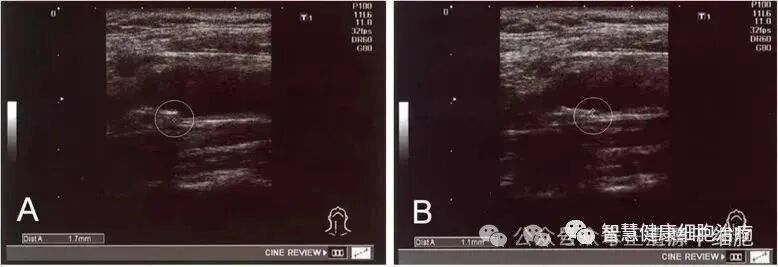

△ 经过治疗,实验中一名患者 IMT 从 1.7 毫米降至 1.1 毫米实验证实:干细胞可以改善血清中的高密度脂蛋白,低密度脂蛋白和残余样颗粒胆固醇水平,调节脂质代谢,能够安全有效地改善动脉粥样硬化。也有专家通过对高胆固醇血症模型小鼠进行干细胞治疗,8周后数据表明,干细胞治疗后的小鼠血清胆固醇水平下降了33%。通过实验证明,干细胞可增强内皮细胞分化,提高内皮细胞活力,加速受损动脉内膜的修复过程,减少或消除斑块的堆积。这主要得益于干细胞的旁分泌功能,它能分泌肝生长因子、白介素8、血管生成素等血管生成因子,促进血管生成与重塑,恢复内皮细胞功能,并减少细胞凋亡。英国伦敦大学的研究人员的一项研究试验中,他们使用荧光标记来追踪一种被称为红系骨髓祖细胞(erythromyeloid progenitor, EMP)的干细胞命运。已知这些细胞会产生红细胞和某些类型的免疫细胞,在培养皿中培养的EMP干细胞也会产生内皮细胞。这一发现,改变了人们对血管是怎样产生的科学认识,使用干细胞产生新的血管和修复受损血管成为可能。 对在母体子宫中自然生长的小鼠而言,干细胞也会产生内皮细胞,并且它们继续位于血管内壁直到成年时。干细胞能清除炎症细胞进而减缓动脉粥样硬化进程,主要表现为减少浸润的炎性巨噬细胞迁移、抑制其活化、改变巨噬细胞的可塑性、打破 M1 / M2 的平衡、调节T/B细胞的免疫平衡。研究显示:动脉粥样硬化从斑块发展到破裂,每一步都伴随着炎症,具有调节、抑制炎症潜力的干细胞疗法自然成了科学家们的重点研究对象。2019年发表于《Journal of Clinical Medicine》的一篇综述显示:目前已有大量研究证实干细胞在动脉粥样硬化上的炎症调节作用,主要机制在于:它能产生大量的抗炎因子(包括IL-10和TGF-β1),同时抑制促炎因子(如IL-1β,IL-6和TNF-α),它还能抑制NK细胞增殖与T细胞分化,从而抑制炎症反应,减缓斑块的形成。而干细胞不仅是“抗炎"好手,它还是一个维持平衡的帮手,它能通过分泌细胞营养因子如KGF、HGF、GM-CSF、Ang-1等去改善细胞的微环境,为免疫系统保驾护航。在动脉粥样硬化的修复过程中提供营养物质,干细胞支持造血功能,加速体内的营养物质交换,提高血管修复效率,促进新血管的生成。来自美国Ochsner-LSU健康科学中心的研究者发现:依托于强大的旁分泌功能,干细胞能重塑患者的血管,维持脑血流量。△ 文章刊登于《Stem Cells》,影响因子6.277研究发现间充质干细胞(hPMSCs)能够表达大量的血管紧张素转换酶-2 (ACE-2),它的产物(Ang1-7)与相关受体结合后,能发挥血管舒张、抗氧化、和抗炎等作用。ACE2/Ang1-7信号也一直被认为是中风治疗的重要靶点。而间充质干细胞所释放的胞外囊泡能够到达脑部,其“运输”的ACE-2及其产物可以维持急性脑中风模型小鼠的脑血流量,缩小脑梗死体积,对防止中风慢性脑结构和功能损伤的延续具有重要意义。△ ACE-2有助于MCAO模型中基于 hPMSCs 的保护

·18例IMT值异常(≥1.1 mm)的患者,在治疗后IMT值均显著减少;